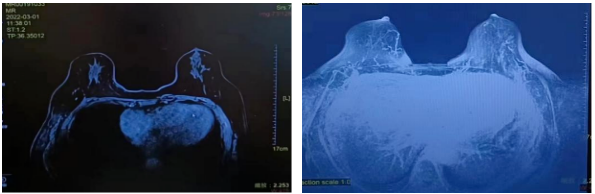

▌2022年3月1日新辅助第3疗程化疗后评价

肿块:无(原左乳内侧肿块,大小2.2cm*1.4cm)。

非肿块强化:无(原右乳内上及内侧肿物旁条片状影)。

同侧腋窝淋巴结:无,(原1枚肿大,大小约2.1cm*2.2cm,结构异常)

2022年3月01日